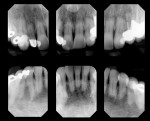

Biomechanical: The examination revealed active caries interproximally on tooth No. 5 and cervical caries on tooth Nos. 19 and 28 through 30. Tooth Nos. 5 through 8 and 20 had defective restorations. Tooth Nos. 3, 11, 28, and 29 had questionable restorations, and tooth Nos. 2 through 7, 13 through 16, 18 through 20, 29, and 30 were structurally compromised due to the size of their current restorations (Figure 7 and Figure 8).2 Of particular note was the stained erosion on tooth Nos. 5, 6, 8, 11, 29, and 30 (Figure 9). The patient admitted to drinking six cans of diet cola and 2 to 4 cups of sugared coffee per day, and she reported episodic xerostomia. In addition, the root canal treatment on tooth No. 2 was failing.

Periodontal: Periodontal pocket depths measured 2 mm to 3 mm in the anterior sextants, and 2 mm to 5 mm in the posterior. Radiographically, generalized mild to moderate horizontal bone loss of between 1 mm and 3 mm was visible. Tooth No. 2, the source of the chief complaint, exhibited circumferential bone loss, with probing depths of 6 mm to 9 mm, secondary occlusal traumatism, and a suspected vertical root fracture. A periodontal diagnosis of AAP type III was made. Recession and abrasion were present on most of her maxillary teeth and the posterior mandibular teeth. This likely resulted from an aggressive toothbrush habit and predisposing anatomy.1 Apical root resorption was noted on tooth Nos. 7 through 9, 11, 23, 24, and 26 (Figure 6).